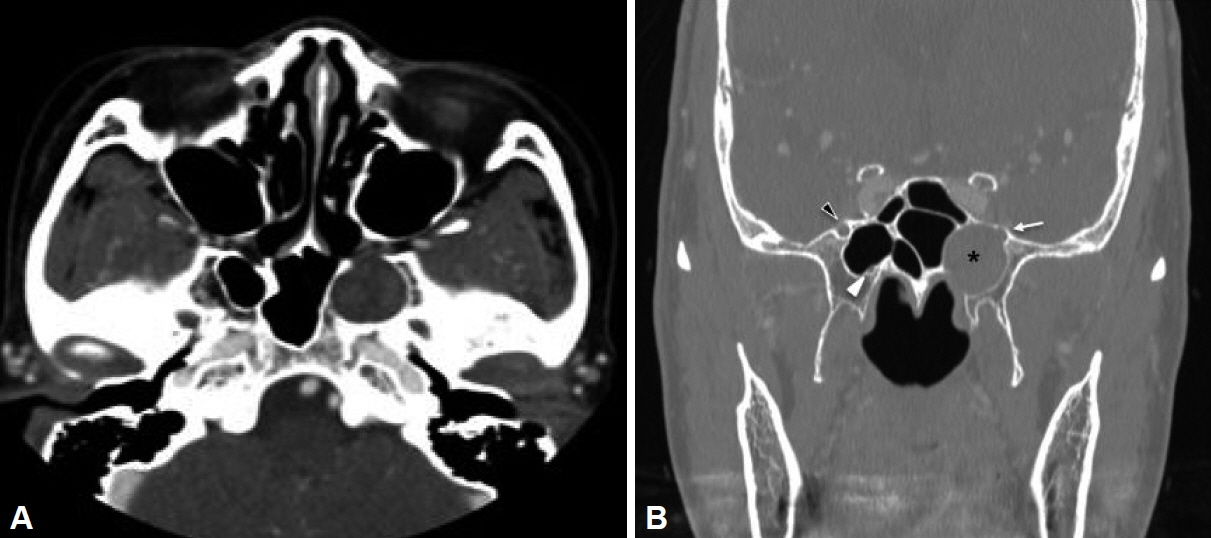

- Schwannomas are benign tumors that can develop in any part of a nerve containing Schwann cells. Skull base schwannomas are rare, representing approximately 4% of extracranial schwannomas. Among these, vidian nerve schwannomas are particularly uncommon, with only a few documented cases. In this report, we describe the case of a 58-year-old female patient who presented with an incidental finding of a skull base mass. The patient’s only symptoms were intermittent headaches and dry eyes. No mass was detected during the physical examination. Radiographic evaluation revealed a neoplasm within the vidian canal, and the lesion’s characteristics suggested a schwannoma. The patient underwent endoscopic resection, and subsequent histopathological analysis confirmed the diagnosis of schwannoma. Follow-up imaging and physical examination showed no evidence of recurrence. This case report highlights a schwannoma located in the vidian canal and extending into the foramen rotundum, which was successfully managed with endoscopic surgery.